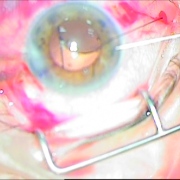

Δευτερογενής ανθέη φακού ιριδικής στήριξης

Δευτερογενής ένθεση φακού

ιριδικής στήριξης

Τομή Κερατοειδούς

Περιφερική Ιριδεκτομή

Ένθεση Φακού

Συρραφή Τομής